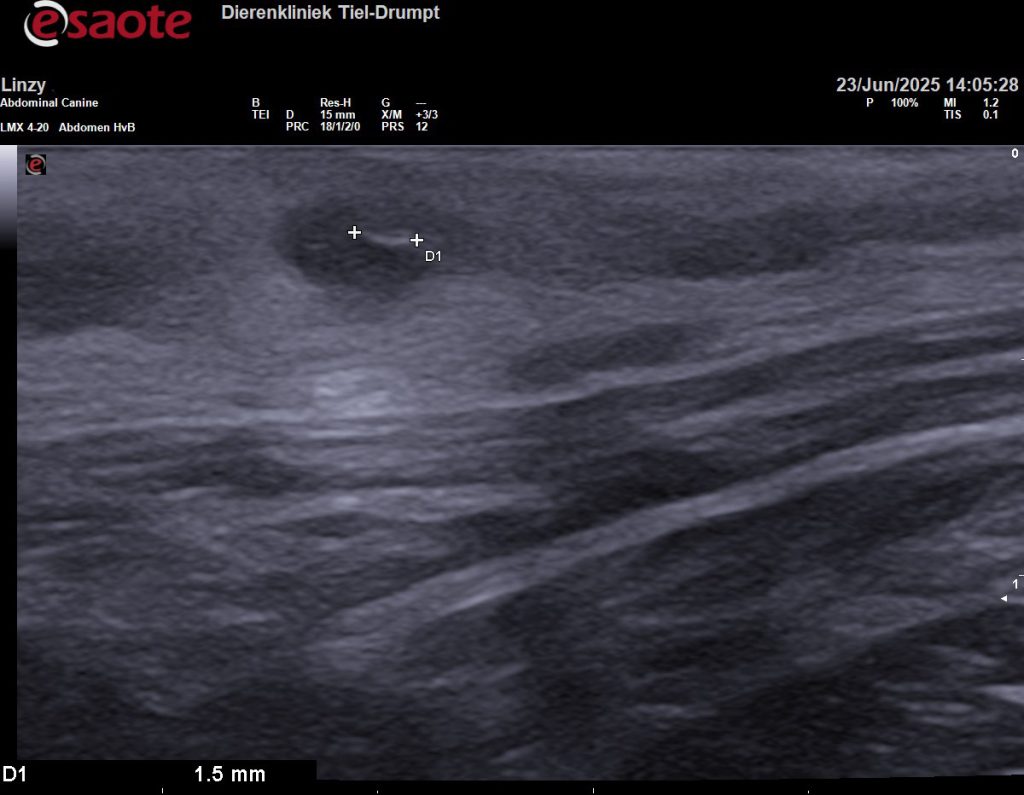

Om meer duidelijkheid te hebben, om te voorkomen dat we voor niks chirurgisch zouden ingrijpen, hebben we de plek eerst bekeken met een echo. Gelukkig hebben we ook een echokop voor zeer veel detail en het beeld bleek eigenlijk heel goed bij een grasaar te passen.

Om zeker te weten dat we alles hadden is het weefsel geopend, voordat we de wond gingen sluiten. In eerste instantie leek het alsof er geen grasaar in het weefsel zat. Maar dit liet maar weer zien hoeveel ons echoapparaat kan vergroten, want op de echobeelden is de diameter van de grasaar 1,5 millimeter en 12,4 millimeter lang. Na een paar sneden vonden we het steekkanaal en de daadwerkelijke grasaar.